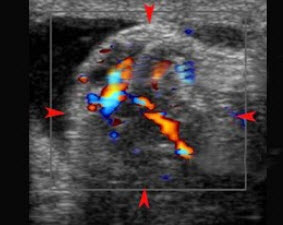

D.左心室腔内有两组乳头肌附着

某患者收缩期超声心动图所示,提示()

A.二尖瓣狭窄

B.二尖瓣关闭不全

C.房间隔缺损

D.动脉导管未闭

E.以上都不是